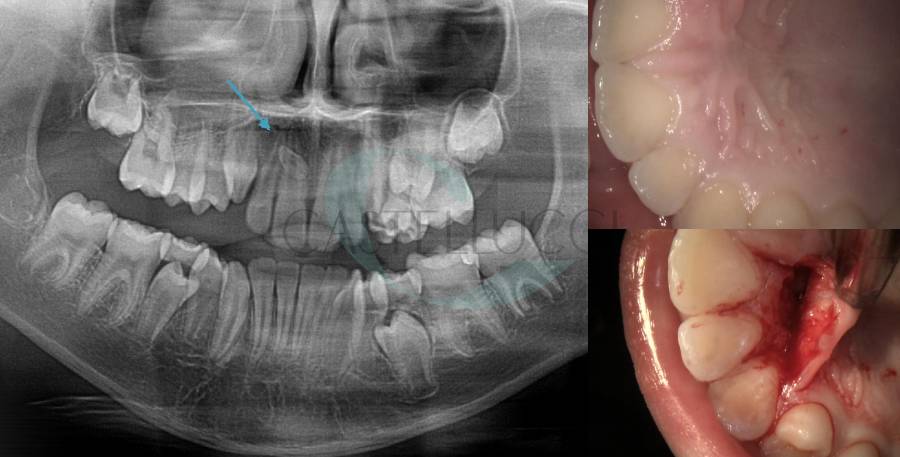

• Disinclusione chirurgica degli elementi dentari permanenti ritenuti